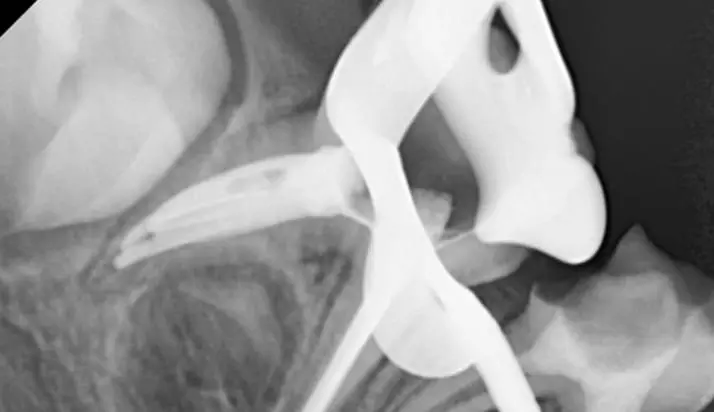

Тимчасові зуби мають ряд особливостей, які не характерні для постійних. Саме тому дитяча ендодонтія відрізняється від дорослої і просте перенесення технік роботи з постійних зубів на тимчасові призводить до серйозних помилок і ускладнень. Наш курс створений для того, аби лікарі впевнено орієнтувались у діагностиці, лікувальній тактиці та її реалізації. Для цього ми розглядаємо питання особливостей анатомії тимчасових зубів, перебігу патології ендодонту тимчасових зубів. В курсі детально подані протоколи лікування, інструменти та матеріали, які використовують для терапії пульпи та кореневих каналів тимчасових зубів. Також дані чіткі критерії визначення терапевтичної чи хірургічної тактики лікування тимчасових зубів. А відеодемонстрація на фантомі та клінічному прийомі дозволить втілити опрацьований матеріал в практику максимально ефективно.